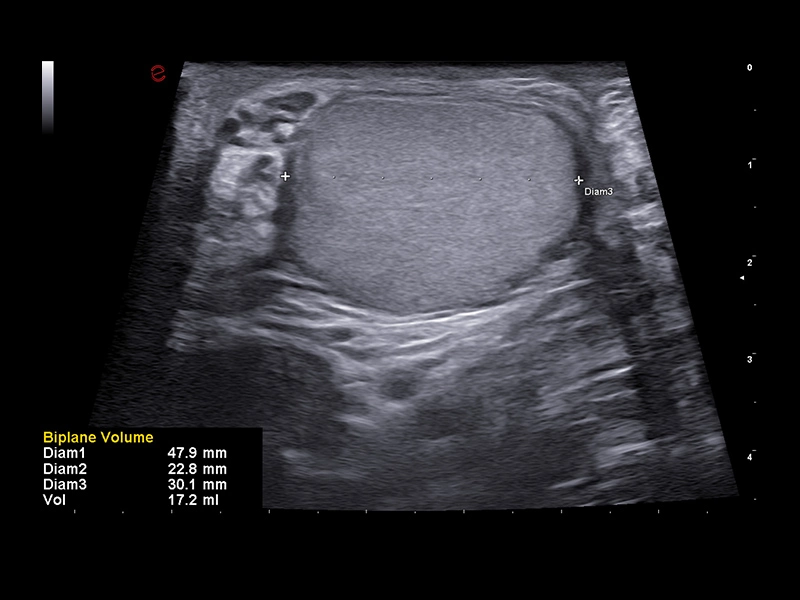

MyLab™9 Platform - High resolution imaging in testis

MyLab™9 Platform - High resolution imaging in testis